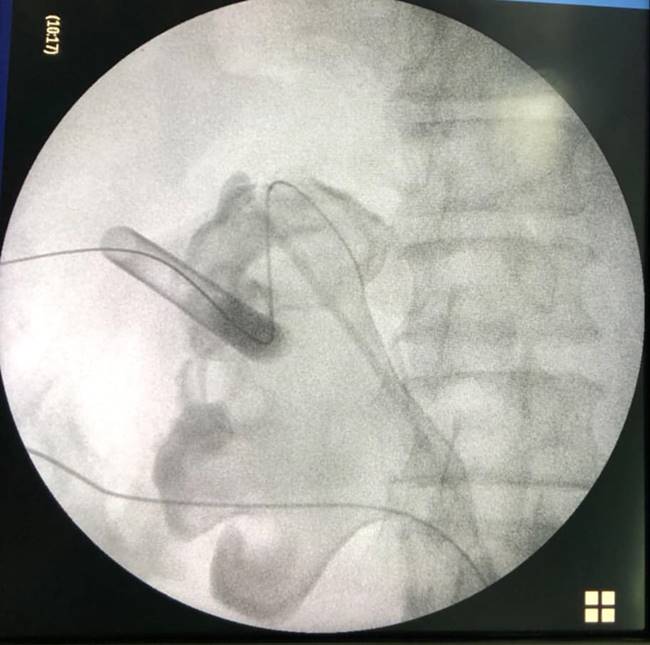

หมอเผยภาพสุดน่ากลัว ผ่าตัดนิ่วจากไตคนไข้ พบมีจำนวนมากจนสามารถเรียกต่อเป็นคำว่า "นิ่ว" ได้ แนะคนไม่อยากเป็นโปรดดื่มน้ำวันละ 6-8 แก้วต่อวัน

เผยภาพนิ่วจำนวนมาก

หลังผ่าตัดออกมาจากร่างกายของคนไข้ที่มีอาการปวดหลังเรื้อรัง

พร้อมกันนี้ คุณหมอได้ระบุข้อความว่า "ของกลางที่พบในคนไข้รายหนึ่ง หลังจากที่ต้องทนทุกข์ทรมานกับอาการปวดหลังและอาการไตเสื่อม คงไม่ต้องบอกว่า......คืออะไร

ขอบคุณโครงการ #ก้าวคนละก้าว ที่นำเครื่องมือผ่าตัดนิ่ว มาสู่รพ.ยะลา

Uro Yala Team"